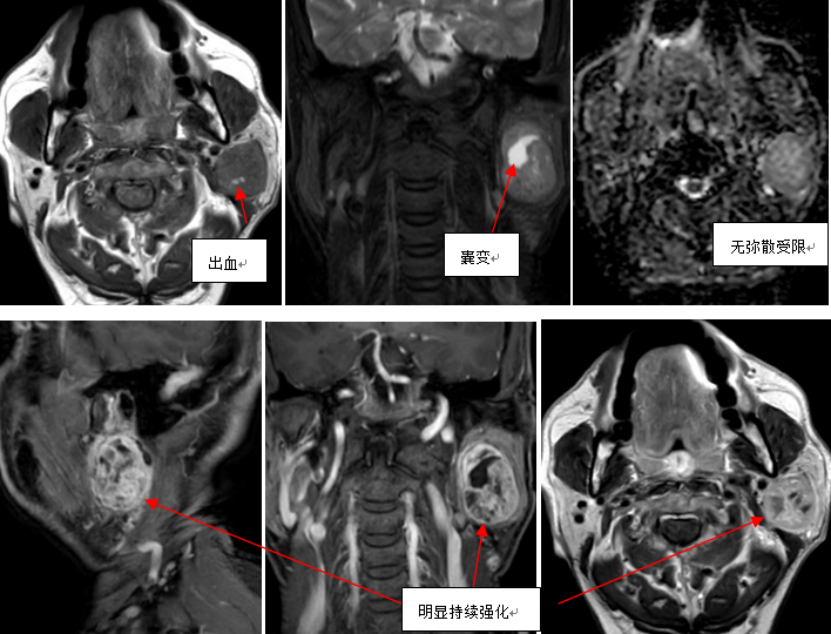

左侧腮腺深叶见混杂团块状异常信号,T1WI为等信号,其内可见片状低信号及点片状高信号,T2WI为稍高信号,内见多发类圆形、点片状高信号,DWI序列呈稍高信号,ADC图呈等及高信号,增强后呈不均匀性明显持续强化,其内可见片状、点状未强化区,肿块边缘呈弧线状包膜样强化,大小约为3.0cm×3.0cm×4.5cm(左右径×前后径×上下径),后缘见弧状T2WI高信号;

左侧腮腺深叶占位伴出血、囊变,考虑偏良性病变:基底细胞腺瘤,多形性腺瘤待排除。

左侧腮腺基底细胞腺瘤